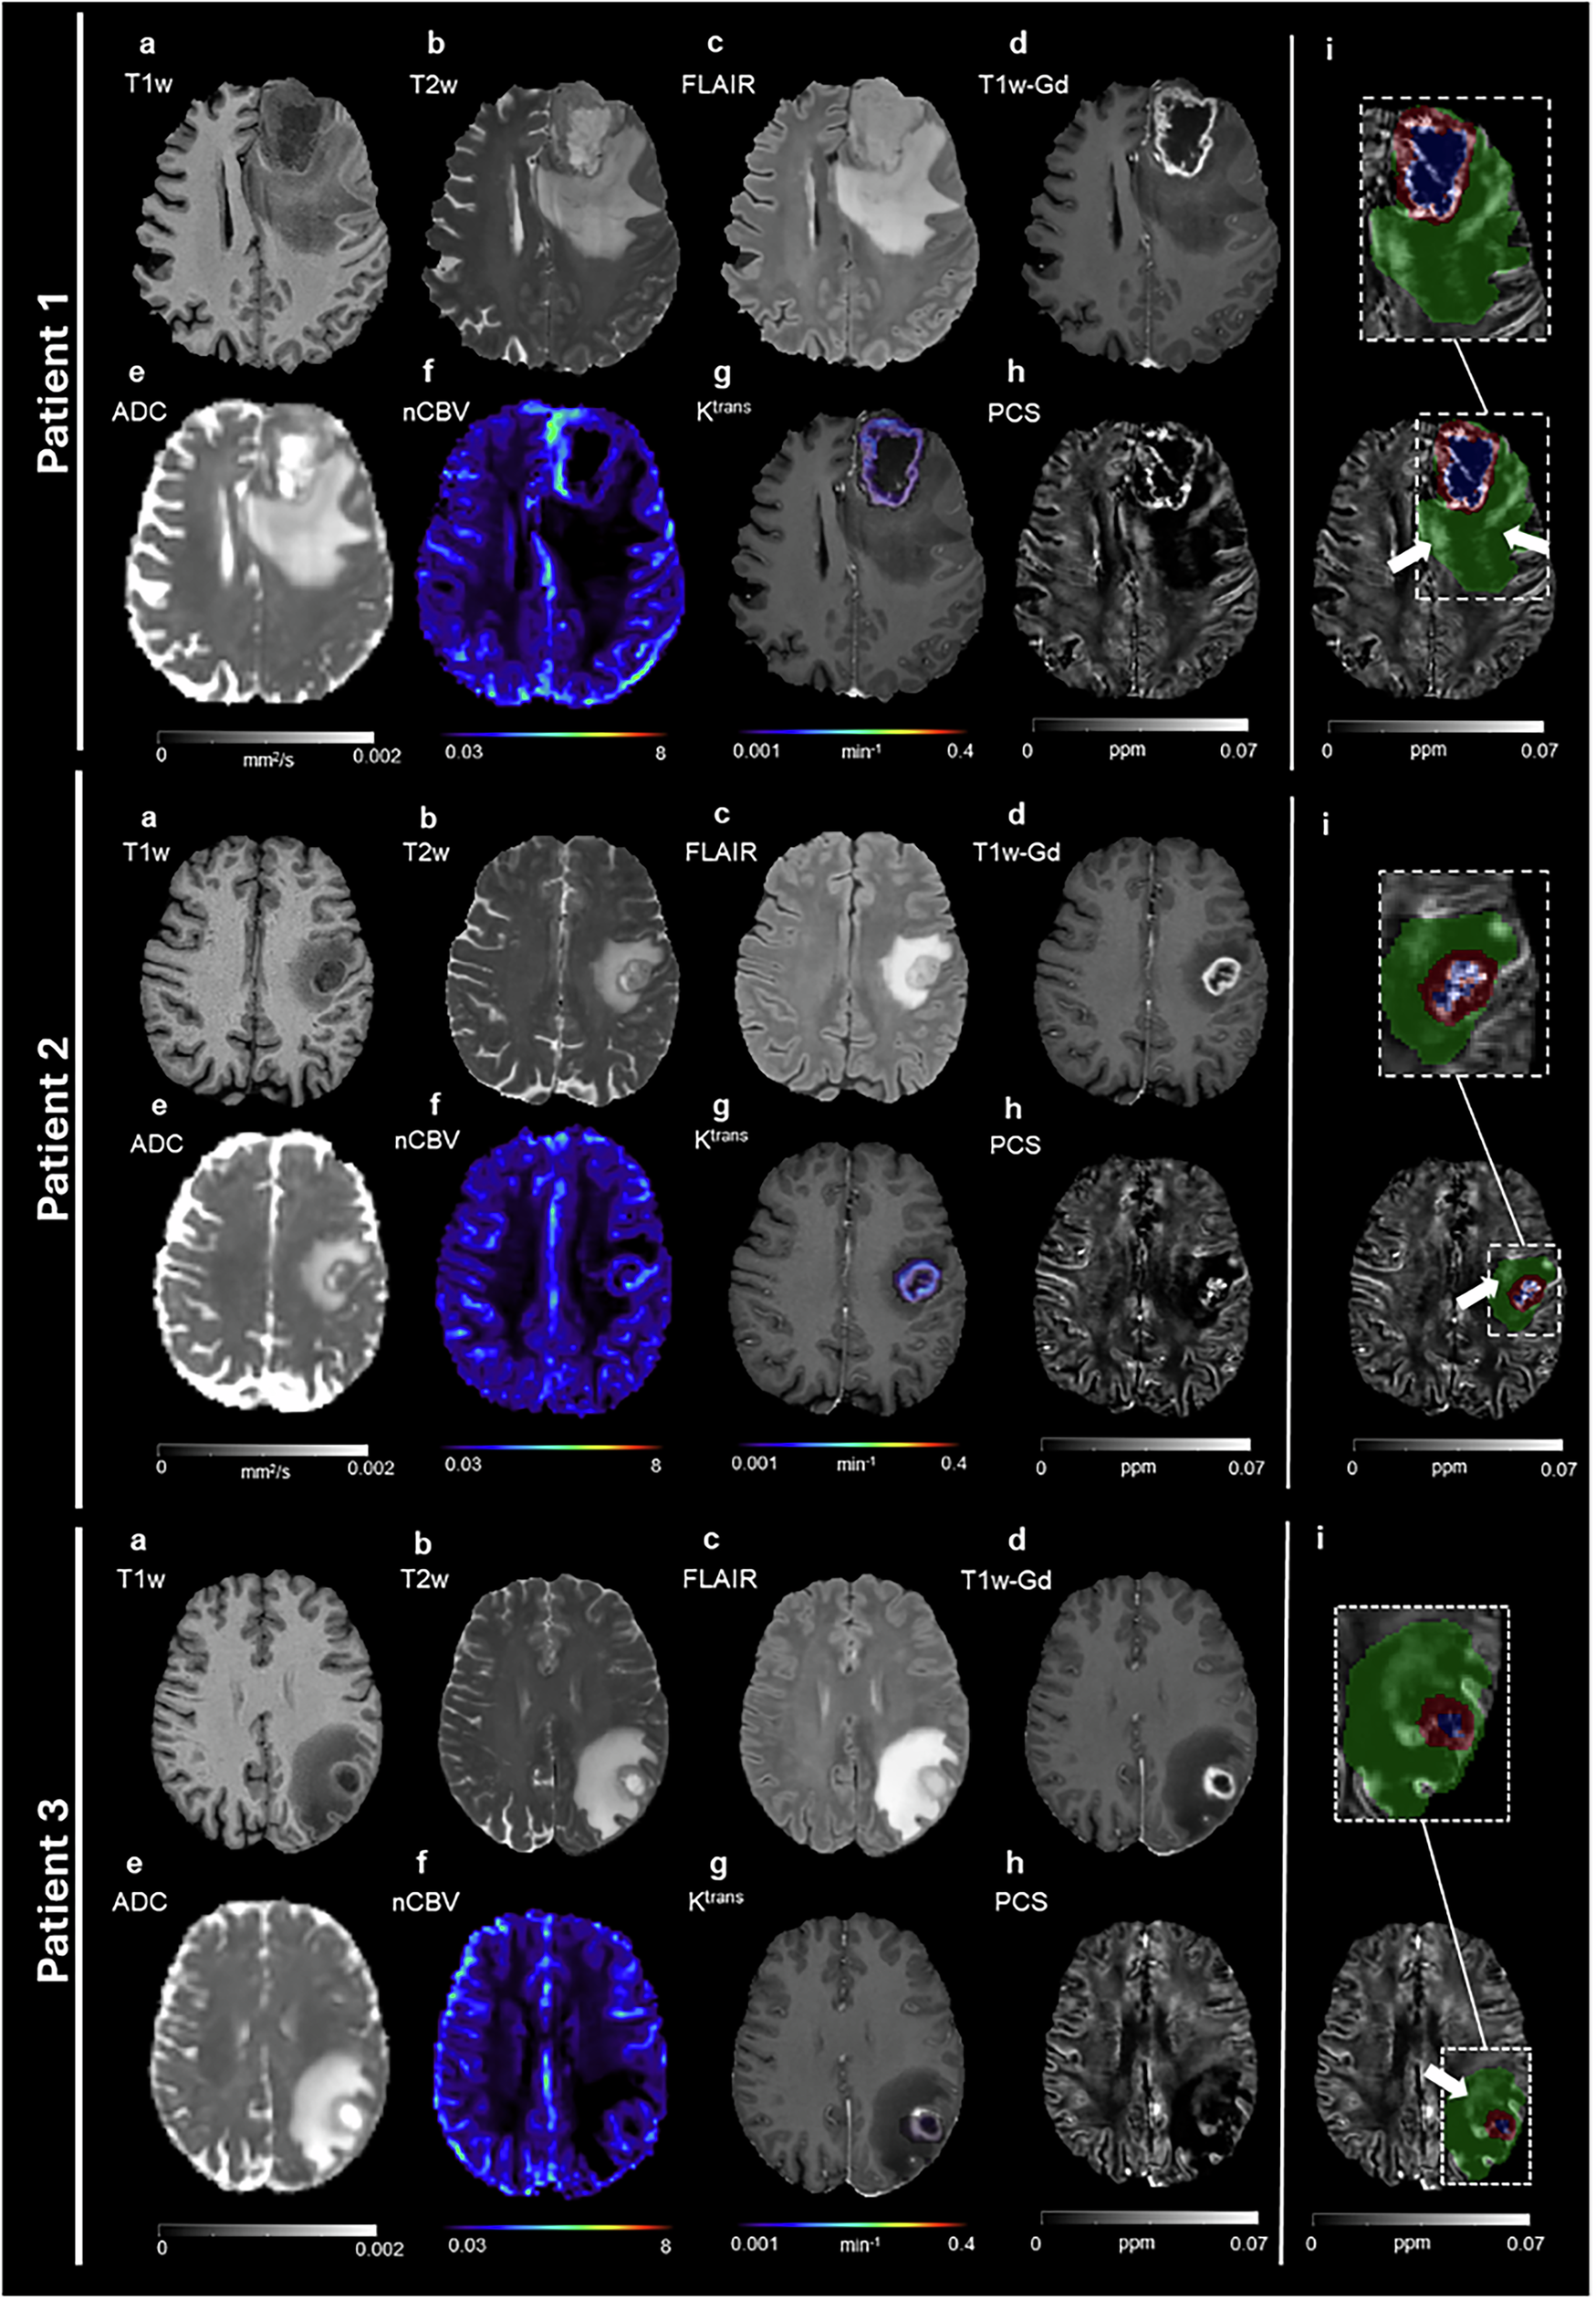

Fig. 1: PCS hyperintensity not visible on conventional MRI.

Axial slices of three representative glioblastoma patients. a T1w; b T2w; c FLAIR; d T1w-Gd; e ADC; f nCBV; g Ktrans (color scale) overlapped to the T1w-Gd (gray-scale); h PCS; i PCS on top of which the color-coded lesion segmentation masks are visualized and a zoomed view (dashed rectangle) of the lesion area (green: edema; blue: necrosis; red: enhancing tissue). White arrows indicate the PCS hyperintensity in edema.